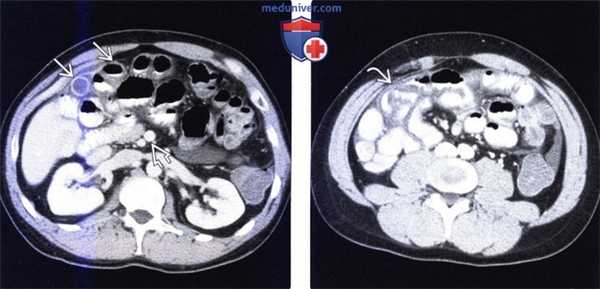

(а) При КТ с контрастированием в аксиальной проекции выявлена транспозиция верхней брыжеечной артерии (указатель) и вены (стрелка).

(б, в) На более низких уровнях при КТ в аксиальной проекции выявлен симптом «водоворота» (стрелка), представляющий собой перекручивание верхней брыжеечной вены и ее ветвей, брыжеечного жира и петель кишки вокруг верхней брыжеечной артерии по часовой стрелке.

(г, д) На рентгенограммах выявлен симптом «штопора» — спиральная конфигурация 4-го отдела двенадцатиперстной кишки и проксимальной части тощей кишки.